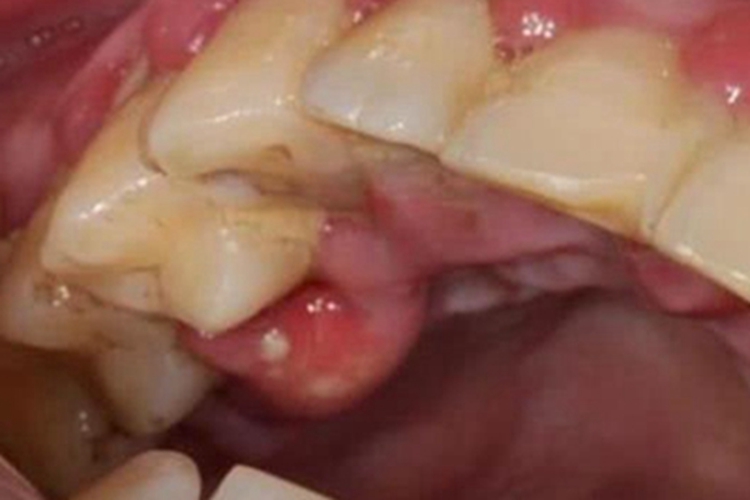

牙槽脓肿患者牙龈潮红、肿胀,局部可出现大包,触之有波动感,自觉患牙疼痛明显,叩痛剧烈,可伴有轻度张口受限、体温升高、白细胞计数增高等。

应急处理:开放髓腔引流通道,缓解根尖部压力;脓肿形成后,需在局麻下切开引流。